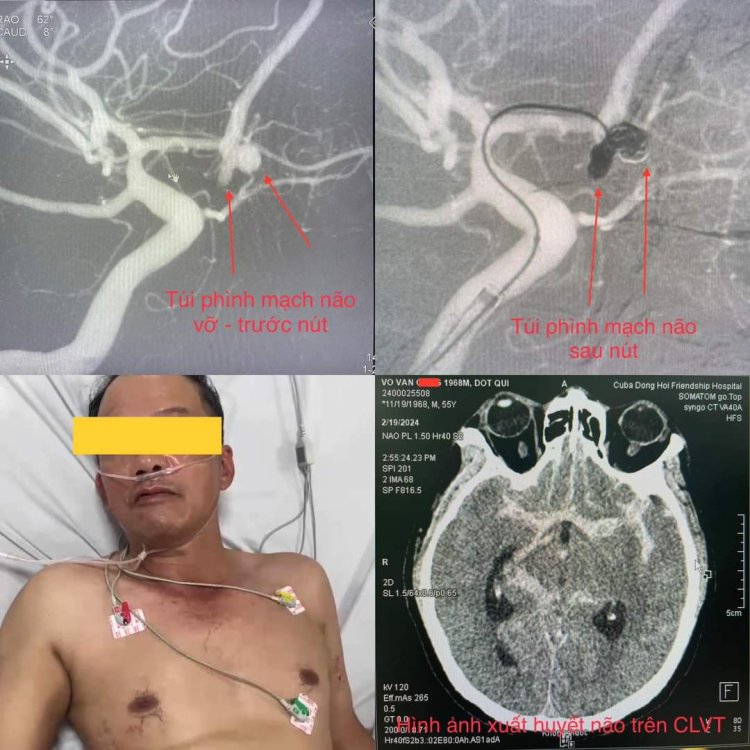

- Nút phình mạch não vỡ

Hình ảnh can thiệp nút phình mạch máu vỡ cho bệnh nhân bị vỡ túi phình mạch não